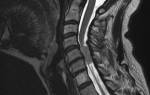

- Шейная мигрень. Это ноющая боль в шее и затылке, которая может возникать из-за сжатия нервов и сосудов, смещения шейных позвонков, что подтверждается магнитно-резонансной томографией. Симптомы могут распространяться на уши, виски и надбровья, также может наблюдаться ухудшение зрения.

- магнитно-резонансная томография;